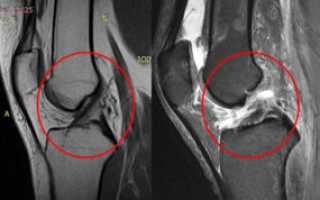

- МРТ. Также весьма эффективным методом является магнитно-резонансная томография. При её проведении используются электромагнитные волны, которые позволяют визуализировать не только плотные, но и мягкие материи. Благодаря этому можно отследить разновидность травмы.

Магнитно-резонансная томография позволяет увидеть все повреждения сустава, в том числе крестообразных связок, в 3d проекции.

- МРТ. Магнитно-резонансная томография является наиболее точной методикой подтверждения диагноза в отношении дегенерации связок колена с вероятностью до 95%;